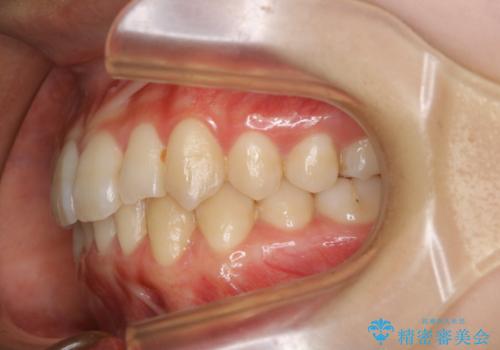

下顎前歯の先天欠損と上顎前歯のクロスバイト:インビザライン治療

- 上の前歯が1本後ろに入ってしまっていることが気になるとご相談にいらした方です。

元々下の前歯が1本欠損しており、上下の噛み合わせや、歯のサイズバランスを考慮しながら治療を行いました。

クロスバイトしている歯が深く噛み込んでおり、この歯を外に出してくる際に強い咬合力が加わると歯が失活する恐れがあることを説明し、合わせて咬筋へのボトックス注入を行いました。

下顎切歯が1本欠損しているため、上顎前歯部を少しずつストリッピングして、上下の噛み合わせ、バランスの向上を図りました。